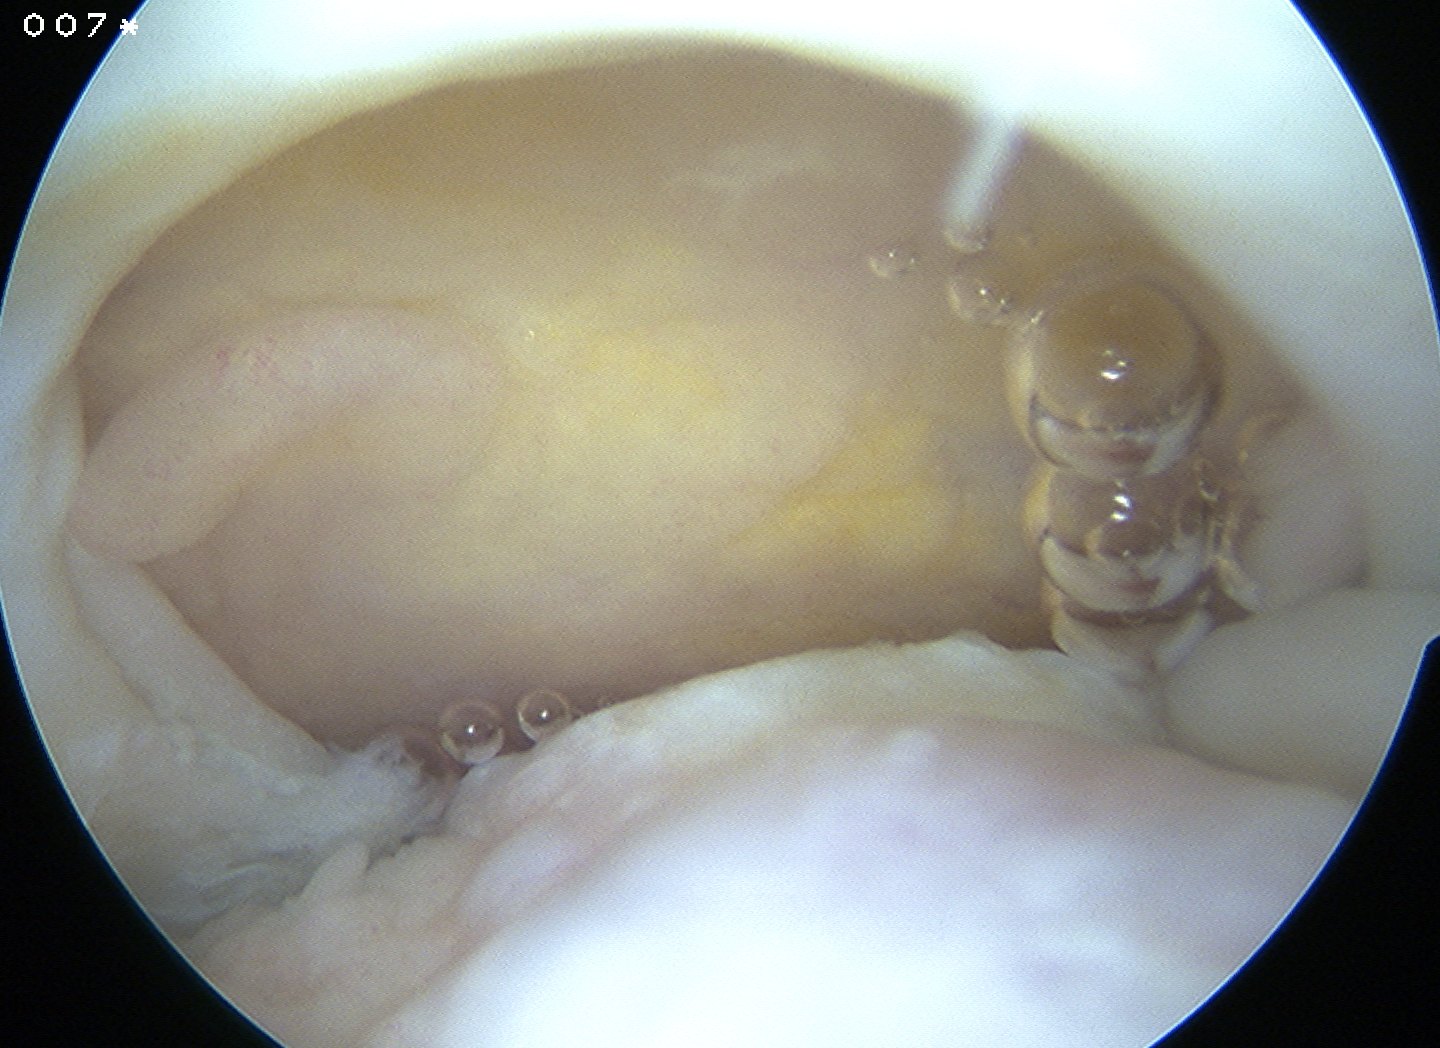

Preparation

Prepare insertion

- debride tendon edges

- debride footprint to punctate bleeding

Assess tendon mobilisation / tear geometry

- perform releases if needed

- as per open surgery

- above and below tendon 1 cm medial to glenoid

- release coracohumeral ligament

Place medial row anchors

- anterior first

- insert 18 G spinal needle and ensure good angle

- just medial to articular cartilage

- stab incision

- insert 5 mm anchor